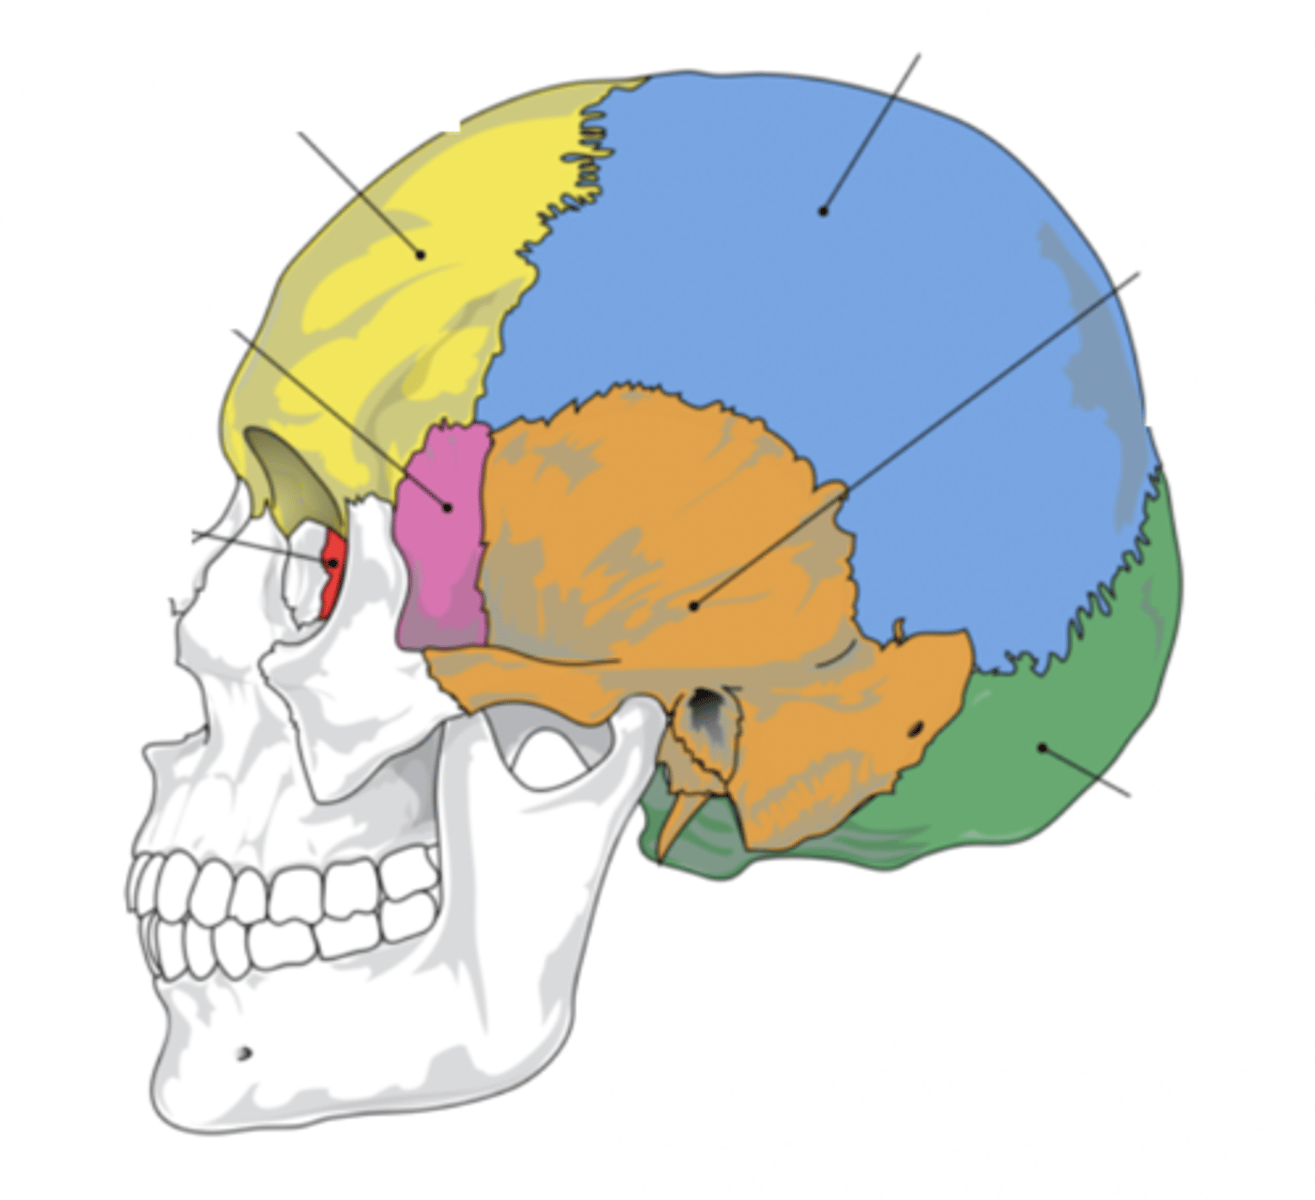

Cranial Bones (8)

- Ethmoid

- Frontal

- Sphenoid

- Temporal (2)

- Occipital

- Parietal (2)

(EFSTOP)

Ethmoid Bone

Forms part of the posterior portion of the nose, the orbit, and the floor of the cranium (red)

Frontal Bone

Bone that forms the forehead (yellow)

Sphenoid Bone

Forms part of the base of the skull and parts of the floor and sides of the orbit (pink)

Temporal Bone (2)

Bone that forms parts of the side of the skull and floor of the cranial activity (orange)

Occipital Bone

Bone that forms the back of the head (green)

Parietal Bone (2)

Either of two skull bones between the frontal and occipital bones and forming the top and sides of the cranium (blue)